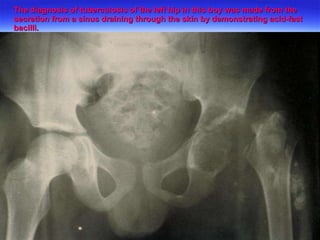

The diagnosis of tuberculosis of the left hip in this boy was made from the secretion from a sinus draining through the skin by demonstrating acid-fast bacilli.